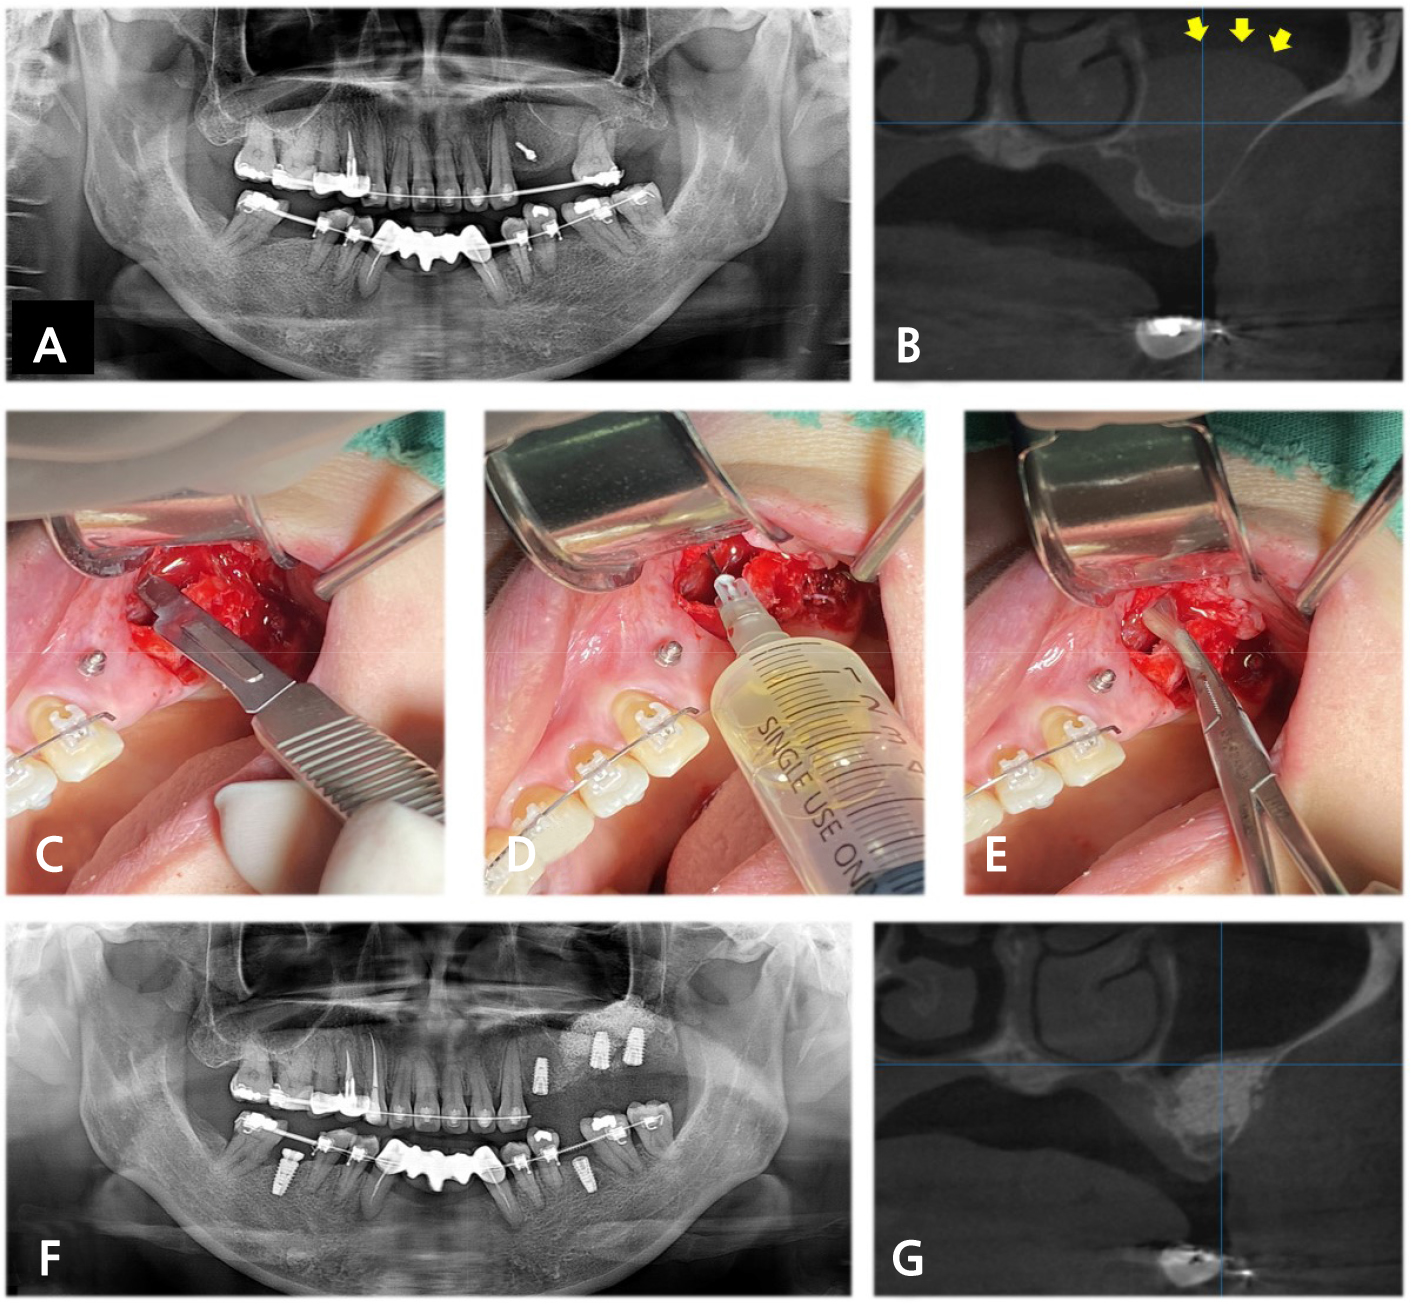

2. Case 1. Preoperative mucous retention cyst

Fig. 1.

(A) Preoperative panoramic radiograph (PAN) and (B) Cone beam computed tomography (CBCT) of patient 1 revealed a dome-shaped opacity in the left maxillary sinus (yellow arrow), (C) Clinical photograph demonstrated incision of the membrane, (D) Aspiration and (E) Removal of mucosal fluid, (F) Postoperative PAN and (G) CBCT demonstrated no remarkable opacity in the left maxillary sinus at four months after sinus augmentation via lateral window (SALW).